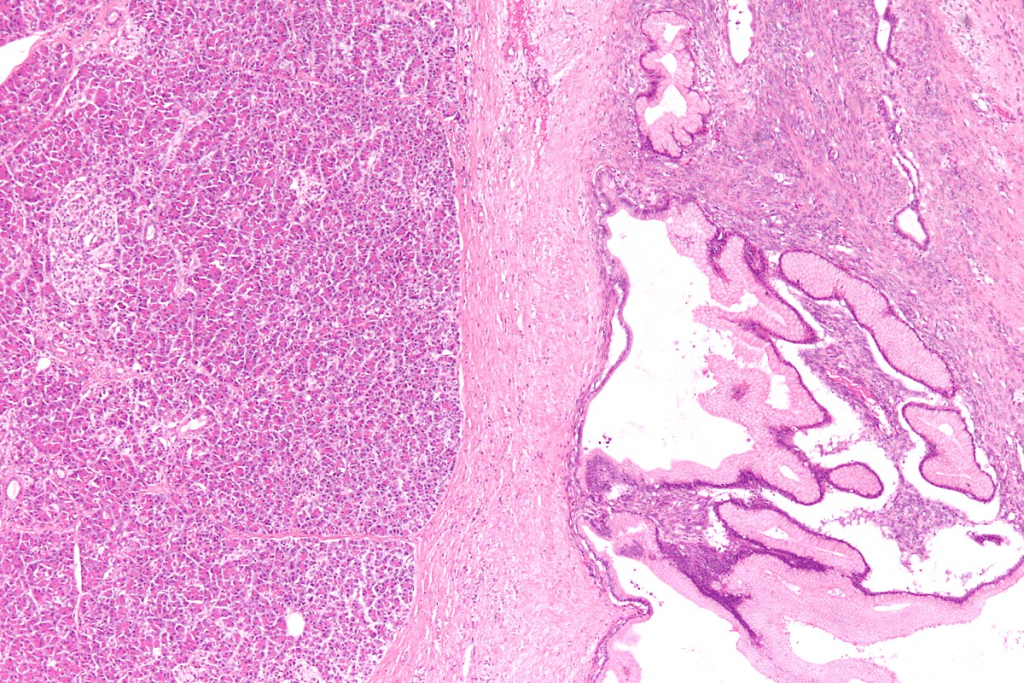

Cutaneous Vascular Lesions

People with Cobb Syndrome often have skin lesions. These can look like port-wine stains. They are a sign of a bigger problem in the spine.

These skin signs can be different. They might be macular port-wine stains or other types of vascular lesions. This includes angiomas, angiokeratomas, angiolipomas, and lymphangioma circumscriptum.